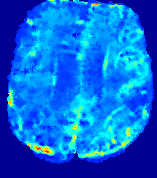

4.2.1 Advection Imaging via Advection

Slice #1Slice #2Slice #3Slice #4Slice #5Slice #6𝐕gt2subscriptnormsuperscript𝐕gt2\|{\bf{V}}^{\text{gt}}\|_{2}Refer to captionRefer to captionRefer to captionRefer to captionRefer to captionRefer to caption(a)Refer to captionRefer to captionRefer to captionRefer to captionRefer to captionRefer to caption(b)Refer to captionRefer to captionRefer to captionRefer to captionRefer to captionRefer to caption(c)Refer to captionRefer to captionRefer to captionRefer to captionRefer to captionRefer to caption(d)Refer to captionRefer to captionRefer to captionRefer to captionRefer to captionRefer to caption(e)Refer to captionRefer to captionRefer to captionRefer to captionRefer to captionRefer to caption(f)Refer to captionRefer to captionRefer to captionRefer to captionRefer to captionRefer to captionRefer to caption000.30.30.30.60.60.60.90.90.91.21.21.21.51.51.5(mm/s)𝑚𝑚𝑠(mm/s)

Figure 12: PIANO effectiveness and robustness testing: advection imaging via advection. Top row shows the ground truth 𝐕gt2subscriptnormsuperscript𝐕gt2\|{\bf{V}}^{\text{gt}}\|_{2} used for simulating pure advection. (a)-(f) refer to the results for 𝐕2subscriptnorm𝐕2\|{\bf{V}}\|_{2} estimated by PIANO, with simulated advection imaging series where Rician noise at levels 0%, 2%, 4%, 6%, 8%, 10% was added respectively.

Our goal here is to determine if PIANO can estimate a known velocity field from a concentration time-series consistent with this velocity field. To this end, for each patient in the ISLES 2017 training set, we treat the velocity field estimated by PIANO as the ground truth velocity field (𝐕gtsuperscript𝐕gt{\bf{V^{\text{gt}}}}), and the first image in the concentration time-series dataset {Cti}superscript𝐶subscript𝑡𝑖\{C^{t_{i}}\} (as described in Sec. 3) is used as the initial condition (C0superscript𝐶0C^{0}). We then simulate ‘advection imaging’ {Cti(Ω)|i=0, 1,, 40}conditional-setsuperscript𝐶subscript𝑡𝑖Ω𝑖0140\{C^{t_{i}}\in\mathbb{R}(\Omega)|i=0,\,1,\,\ldots,\,40\}, i.e., we create a time-series of concentration images driven by the velocity 𝐕:=𝐕gtassign𝐕superscript𝐕gt{\bf{V}}:={\bf{V^{\text{gt}}}} only via the advection PDE:

We further simulate noisy concentrations by adding Rician noise [24] with variances equalling 2%, 4%, 6%, 8%, 10% of the originally simulated concentrations {Cti}superscript𝐶subscript𝑡𝑖\{C^{t_{i}}\}. We then test how well PIANO can estimate the underlying velocity field via Eq. 15 with the same model settings (except without estimating the diffusion) as in Sec. 3 given the original and the noisy concentration time-series. Fig. 12 shows the estimated 𝐕est2subscriptnormsuperscript𝐕est2\|{\bf{V}}^{\text{est}}\|_{2} for one patient. Fig. 11 (a) shows the summarized estimation results for all 43 patients. PIANO almost perfectly captures the underlying velocity field, and maintains excellent performance even when estimating from concentrations with varying noise levels.